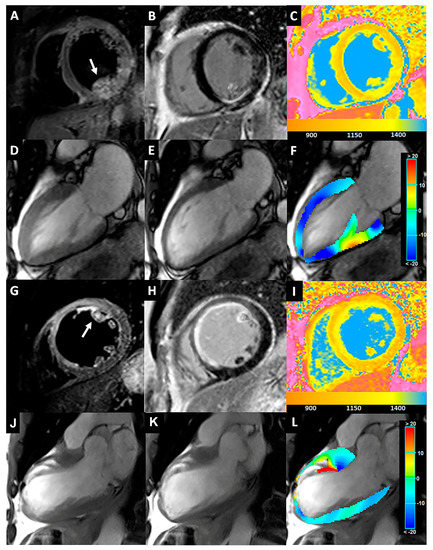

Two cases of iPPM involving the AL- and PM-PPMs are reported in Figure 5.

Figure 5. (AF) A 55-year-old man with inferior STEMI for RCA occlusion. T2-STIR (A) and LGE (B) images acquired on the short-axis views revealed LV inferior wall edema and enhancement, respectively, with PM-PPM involvement (arrow). In the corresponding nT1 map (C), PM-PPM showed a similar increase in the nT1 values compared to the infarcted myocardium (yellow color). The CineMR images acquired on the long-axis view in the end-diastolic (D) and end-systolic (E) phases showed hypokinesia of the lower wall and impaired contraction (lower shortening and thickening) of PM-PPM, as shown in the colorimetric map of longitudinal strain analysis by the tissue tracking automatic module (F). (GL) A 61-year-old with extensive anteroseptal STEMI due to LAD proximal occlusion. A large area of transmural myocardial edema and mid-wall/subendocardial enhancement of the anteroseptal LV wall are visible in the T2-STIR (G) and LGE images (H), respectively, with AL-PPM involvement (arrow). The nT1 map (C) demonstrated a strong increase in the infarcted area, included in the AL-PPM (yellow color). AL-PPM is akinetic on the cineMR images acquired on the long-axis view in the end-diastolic (J) and end-systolic (K) phases, as highlighted by a red color depicting the severely reduced PPM-ls (L). STEMI: ST-elevation myocardial infarction; RCA: right coronary artery; LGE: late gadolinium enhancement; LV: left ventricular; PM: posteromedial; PPM: papillary muscle; LAD: left anterior descending artery; AL: anterolateral; PPM-ls: PPM-longitudinal strain.